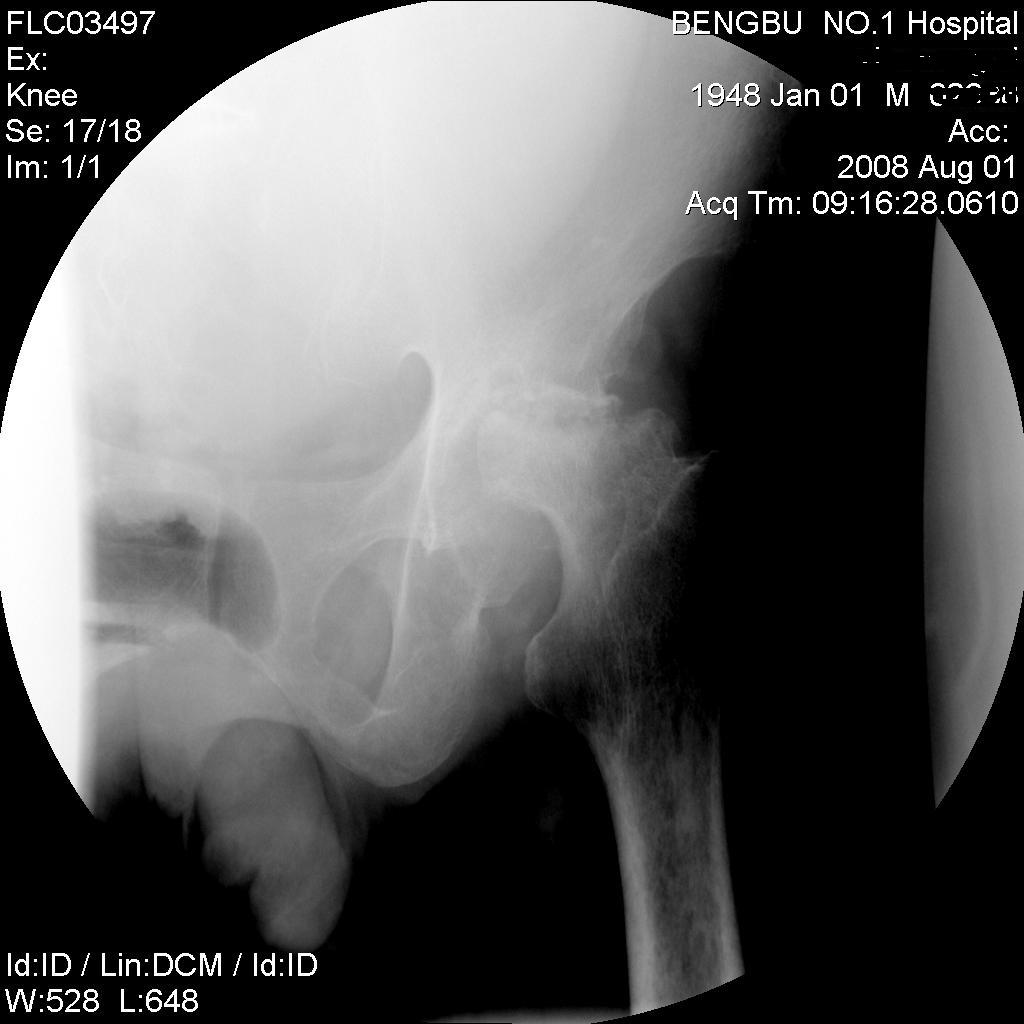

标题: X4652:左股骨头病变,请分析。

男,60岁,左髋部疼痛半年余,近期加重不能行走,爱喝酒。

股骨头持重面塌陷,其外上缘部分骨质缺损且碎裂,骨质密度不均匀增高,髋关节间隙变窄,股骨头向外移位。申通线不连续。结合病人有酗酒史,考虑股骨头无菌性坏死伴骨关节病。